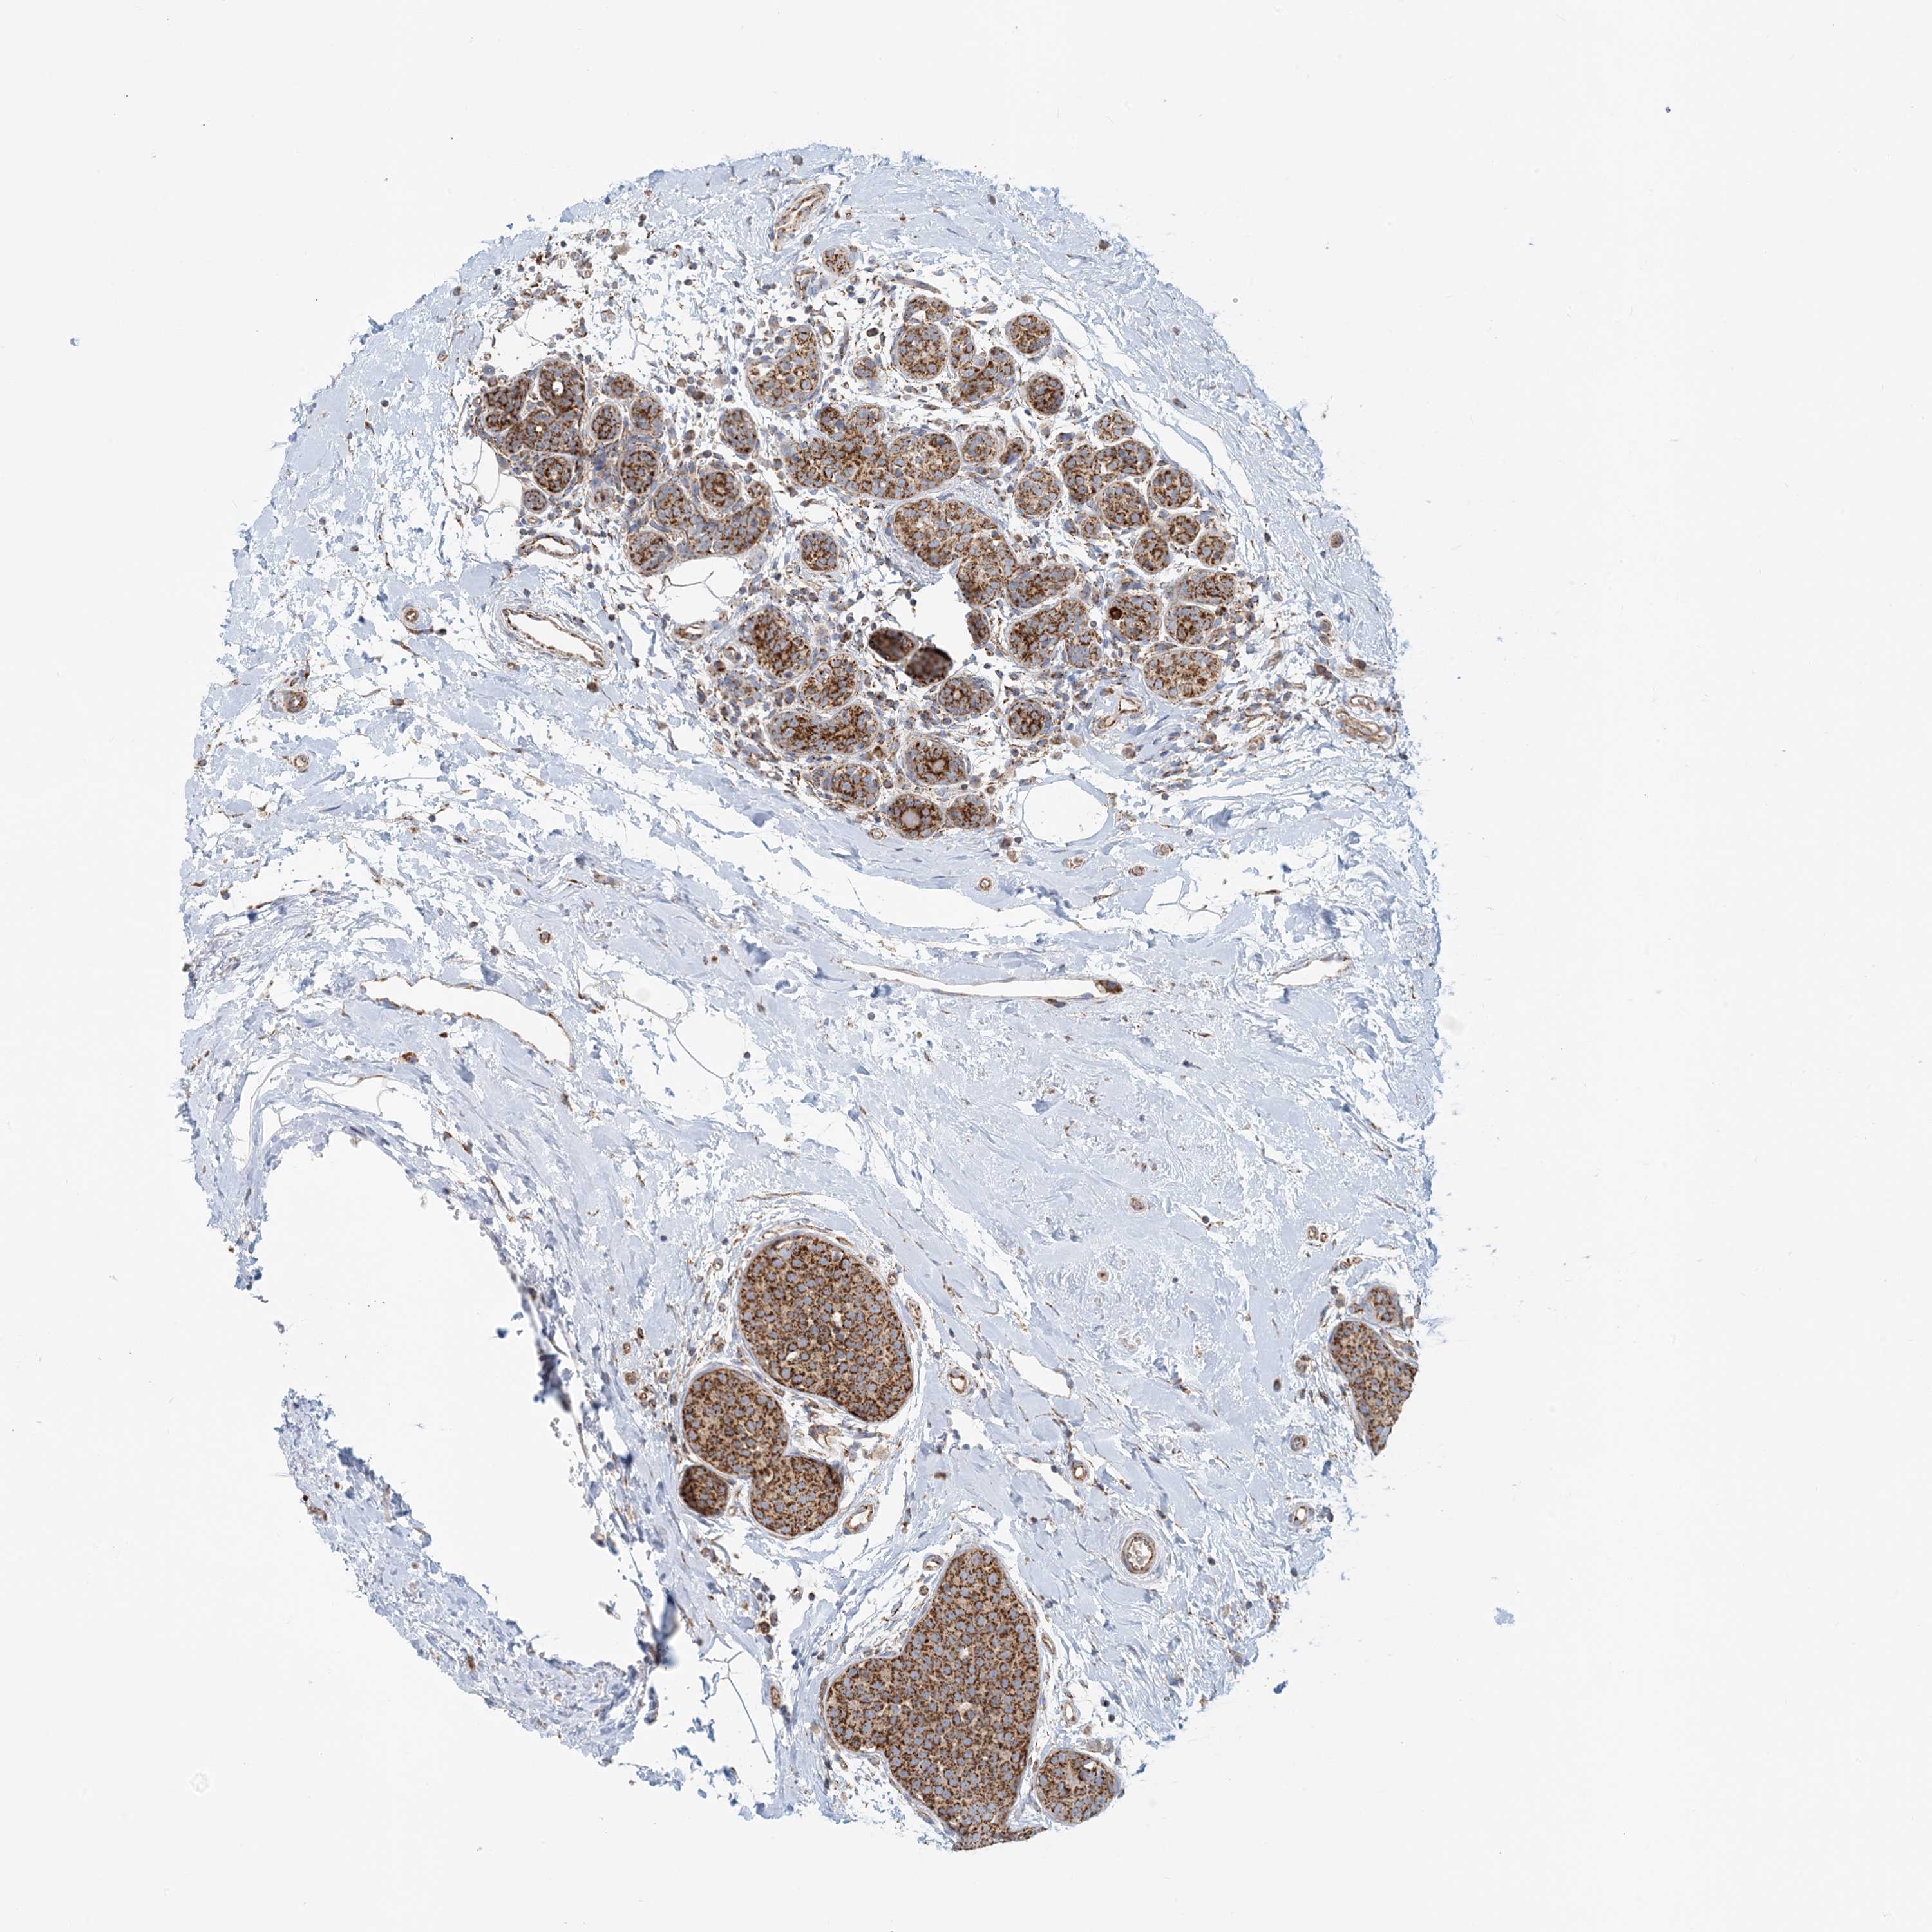

CANCER BREAST CANCER Show tissue menu

BRCA TCGA BRCA VALIDATION PROTEIN EXPRESSION

ANTIBODIES

AND

VALIDATION